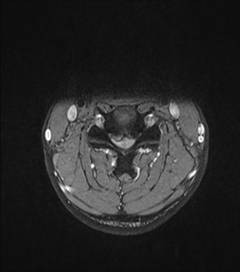

中年男性41歲,因“行走不便2年,加重伴雙手麻木2周”之主訴入院,癥狀主要為:頸部疼痛、僵硬,雙下肢無力、行走不穩(wěn),雙手麻木,協(xié)調(diào)性差,右手握筆困難。入院查體:步態(tài)不穩(wěn),C3-C7壓痛、叩擊痛,肢痛溫覺減退,雙上肢肢肌力5-級,雙下肢肌力4-級,肌張力增高,雙下肢腱反射亢進(jìn),病理征(+),行頸前路小切口突出椎間盤切除、前路頸椎橋形鎖定植骨融合(ROI-C假體),無需前路鋼板,術(shù)后四肢麻木明顯緩解,右上肢精細(xì)動作明確增強(qiáng),可寫字,行走不穩(wěn)消失,肌力基本正常,頸部活動度無明顯受限。(圖1、圖2)

圖1:術(shù)前頸椎MRI提示頸椎退行性變,C4/5椎間盤突出、脊髓出現(xiàn)高信號改變,C4硬膜囊受壓變形。